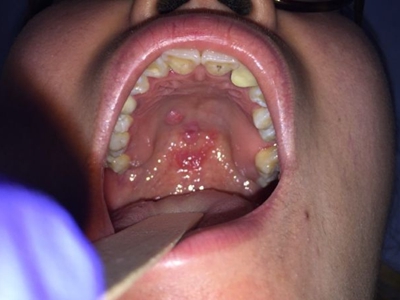

梅毒黏膜斑是二期梅毒最常见的口腔损害。可发生在口腔黏膜的任何部位,以唇黏膜最多见,其次为软腭、舌背、舌底等部位。损害呈灰白色、光亮而微隆的斑块,圆形或椭圆形,直径约1cm,边界清楚。易发生糜烂或浅表溃疡,表面覆盖灰白色假膜,周围有红晕。黏膜斑常为多个,内含有大量梅毒螺旋体。